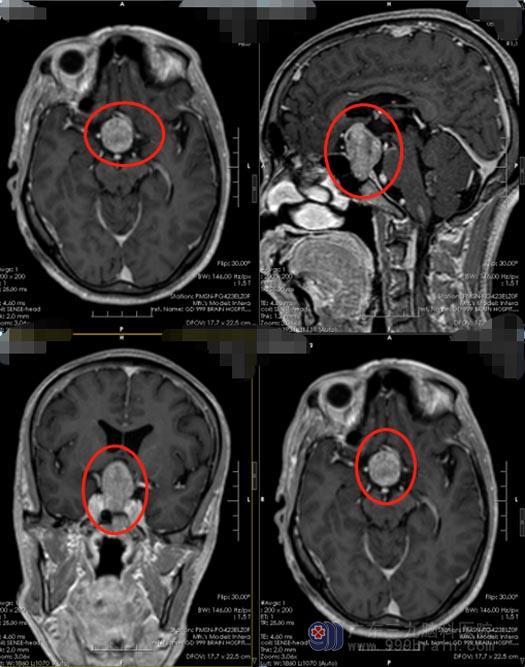

近一周时间,郑大哥发现自己偶尔会出现头晕伴恶心,这下,他有些紧张了,立即去当地医院检查,头颅MR检查提示“鞍区占位性病变,垂体瘤可能”。郑大哥不相信这样的事会发生在自己的身上,为了证实病情,他来到了广东三九脑科医院神经外五科,经过进一步的检查后,医院副院长、神经外五科主任鲁明认为患者患垂体瘤的可能性非常大。

郑大哥有明确的手术指证,应尽早手术,否则病情会向更为严重的方向发展。完善相关的术前准备后,由鲁明主刀为患者行全麻下“经鼻蝶鞍区占位切除术,”手术非常成功,术中出血少。术后郑大哥恢复很快,也没有出现手术并发症。